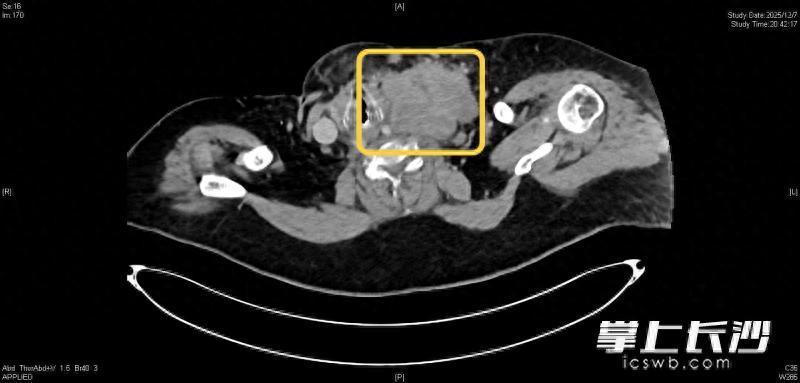

急诊科副主任、主任医师丁宁介绍,患者体重超过100公斤,无明显诱因逐渐出现活动后呼吸困难,症状持续加重,入院时全身发绀、“点头样”呼吸、大汗淋漓,脉搏达165次/分(正常为60~100次/分),呼吸达31次/分(正常为12~20次/分),血氧饱和度降低,二氧化碳分压增高,白细胞远高于正常值。在体格检查时,医生发现患者颈部存在一个较大肿块,CT检查显示,其左颈部至左锁骨上区有一个约10厘米×9厘米的巨大包块,气管后方也有一个4.4厘米×4厘米的巨大包块,两个包块严重压迫气道、影响呼吸。